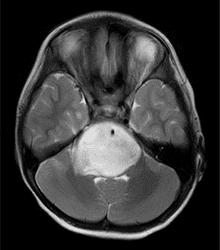

毛様細胞性星細胞腫 | 上衣腫 | 髄芽腫 | 脳幹部腫瘍 |

胚細胞性腫瘍 | 脈絡叢乳頭腫 | 頭蓋咽頭腫 | その他の小児脳腫瘍 |